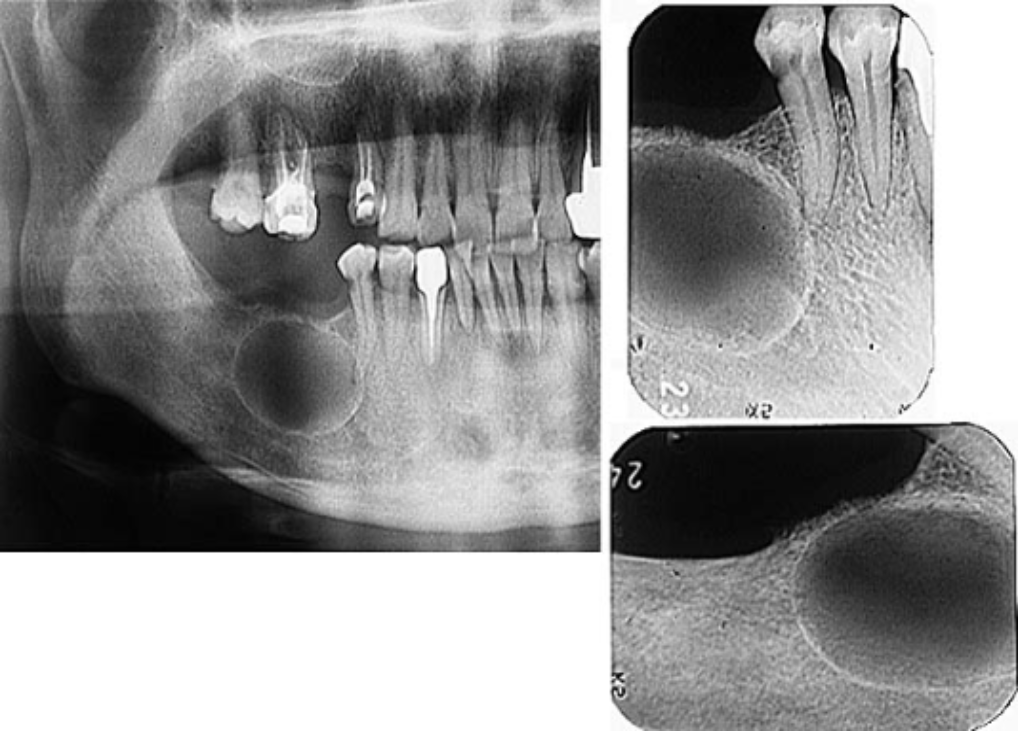

There was a recurrence of the cyst in a few months and. Odontogenic keratocyst okc or keratocystic odontogenic tumor kcot. Large odontogenic keratocysts sometimes are treated initially by cystotomy and insertion of a drainage tube which can promote shrinkage of the lesion and fibrous thickening of the cyst wall before subsequent total removal.

Surgical Removal of Odontogenic Keratocyst. Odontogenic keratocysts OKCs are benign intraosseous odontogenic lesions that have a locally aggressive behavior and exhibit a high recurrence rate after the treatment. Odontogenic keratocysts can initially be treated with incisional biopsy and decompression by installing a polyethylene drain to allow subsequent reduction of the cystic cavity size resulting in thickening of the capsule which allows a later easy removal withapparently lower relapse rate waldron.

Cyst can be removed by open as well as endoscopic approach. Imaging studies and a biopsy were obtained at the hospital. Large odontogenic keratocysts sometimes are treated initially by cystotomy and insertion of a drainage tube which can promote shrinkage of the lesion and fibrous thickening of the cyst wall before subsequent total removal.

The excision of the overlying mucosa. Odontogenic keratocyst is one of the most aggressive odontogenic cysts with a high recurrence rate this was explained histopathologically as it typically shows a thin friable wall which is often difficult to enucleate from the bone in one piece and have small satellite cysts within the fibrous wall. Immediate mandibular reconstruction with a corticocancellous iliac crest bone graft.

It most often affects the posterior mandible and most commonly presents in the third decade of life. Osteotomy in the trigonoretromolar region until the exposure of the lesion. Enucleation of the lesion.